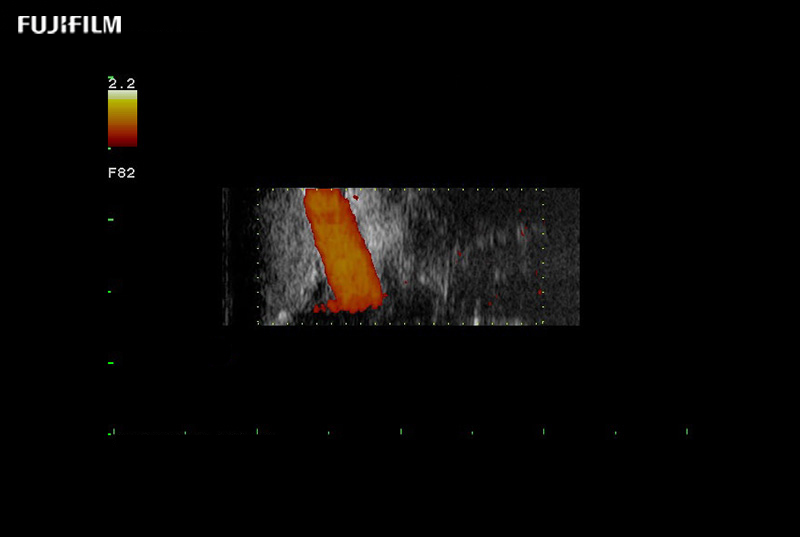

Exclusive 10mm side‐fire linear array transducer with 2.87mm diameter is ideal for real‐time visualization through and behind structures and instant, scalable definition of anatomy and vascularity including the ability to delineate and define tumor margins.

Main Specifications: